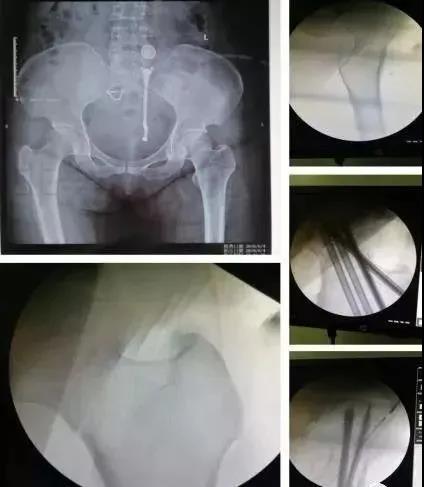

2)骨盆骨折

30min,三个决定:

- 开放性骨折,立即止血;

- 骨盆制动(10-15min);

- 观察10-15min,血流动力不稳定,能否手术?

血流动力学稳定,在7天内手术?

3)髋臼骨折(伤后5-7天)

- 人体最大的负重关节,精确复位可达到关节的最佳匹配,确保正常力学性能;

- 影像学移位程度大,不匹配>2mm--手术;

- 髋关节脱位,髋臼后壁骨折并股骨头骨折,复位后关节仍然不稳,或关节腔有游离骨块--手术。

并发症:异位骨化18-90%;股骨头坏死3-9%